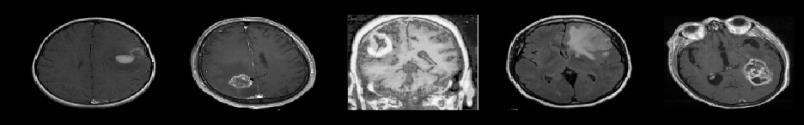

3.1Data Acquisition and Pre-processing: ThefirststepinbuildingthebrainTumorsdetectionmodelinvolvesacquiring a dataset of MRI images containing both Tumors and non-Tumors samples. The notebook may include code snippets for downloading or importing the dataset.[23] Subsequently, the data is pre-processed to ensure consistency and improve model performance. Pre-processing steps may include resizing images, normalization, and augmentation to increase the dataset'sdiversityandrobustness.

3.2Feature Extraction with VGG16: The VGG16 pre-trained model is employed for feature extraction from the MRI images.ThenotebookwouldlikelyincludecodetoloadtheVGG16modelalongwithitsweightstrainedonImageNet.The MRI images are passed through the VGG16 model to extract high-level features. [6] The output features from one of the intermediatelayersofVGG16maybeusedastheinputforthesubsequentclassificationlayer.

3.3Transfer Learning:Transfer learning isutilized toadapt the pre-trained VGG16model to thespecific task of brain Tumors detection. [19] The notebook may include code for fine-tuning the VGG16 model on the brain MRI dataset. This involves freezing the weights of the convolutional layers and training only the newly added classification layers. [9] Additionally, techniques such as learning rate scheduling and early stopping may be implemented to optimize model training.